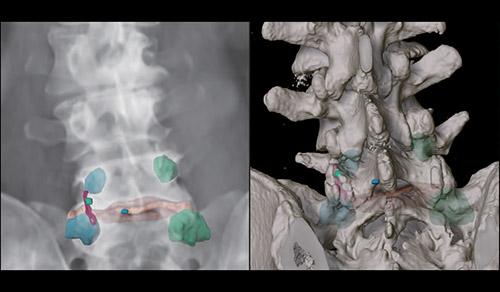

Innovative technologies and alternatives to traditional treatments are transforming the diagnosis and management of neurological conditions. In 2025, NewYork-Presbyterian physicians and surgeons from Columbia and Weill Cornell Medicine used sonication and convection-enhanced delivery to penetrate the blood-brain barrier, validated an adjunctive treatment for subdural hematoma, broadened access to spine surgery, advanced experimental therapies for neurodegenerative diseases, and more. Our specialists have been steadfast in reshaping the fields of neurology and neurosurgery in the pursuit of better patient outcomes and enhanced quality of care.

From cutting-edge research to compassionate patient practice, neurologists and neurosurgeons from Columbia and Weill Cornell Medicine are at the forefront of developing and applying the most advanced approaches to treat debilitating conditions affecting the brain and spine. With a broad range of focus on neurodegenerative and neurovascular disorders to malignant tumors, our innovative and advanced care is leading to new treatment options and enabling patients to achieve the best possible outcomes.